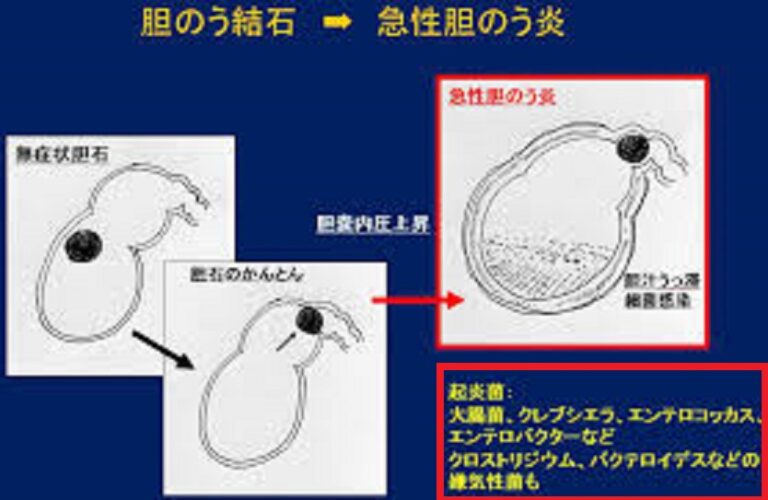

データは非常に単純かつ直接的です。結石、つまり有名なによる胆管閉塞のケースの実質 90% は最終的に胆嚢炎 (この場合は結石性胆嚢炎と呼ばれます) を引き起こします。

胆石は、胆汁物質の生成や濃度の変化、および/またはコレステロールを増加させる脂肪分の多い食品の過剰摂取による胆汁物質の硬化によって形成されます。そして、この状態は無症状であることがほとんどです。

胆嚢が閉塞すると、炎症を起こすまで収縮して正常に空にすることができません。最初の症状は腹痛であり、腹痛が激化し、吐き気や嘔吐も引き起こします。発熱はある場合もあれば、ない場合もあります。